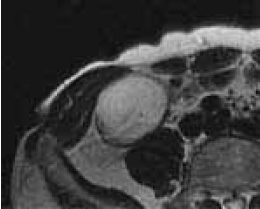

Plain CT: 3*2cm major oval space-occupying lesions are detected in the ileocecum. The internal resorption level is relatively uniform and is associated with the calcification of the wall partly (Figure 1).

Figure1. Plain CT